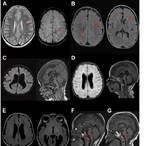

한국인 1만5천명 유전체 분석…미규명 소아 신경발달장애 원인 ‘비암호화 변이’ 규명

- 2026-03-30 08:26

- 노재영 기자